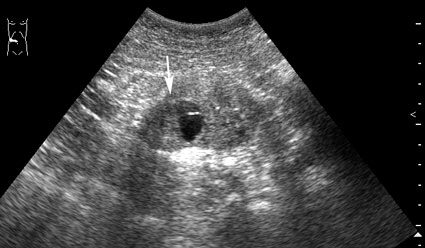

Пациент - мужчина 55 лет, новообразование - случайная находка.

При ультрасонографии в нижнем полюсе правой почки обнаружена киста с тканевым компонентом (стрелка)

1.jpg (23.74 КБ) 997 просмотров